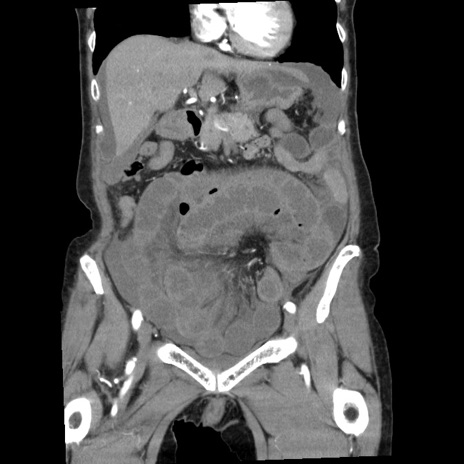

症例1(冠状断像)

【症例】80歳代女性

【主訴】腹痛

【現病歴】8時間前から腹痛あり来院。

【既往歴】糖尿病、脂質異常症、子宮体癌にて子宮全摘術

【身体所見】意識清明・会話良好だが腹痛で苦悶様、全腹部にわたって反跳痛と圧痛あり

【データ】WBC 13600、CRP 0.14、LDH 224、CK 90